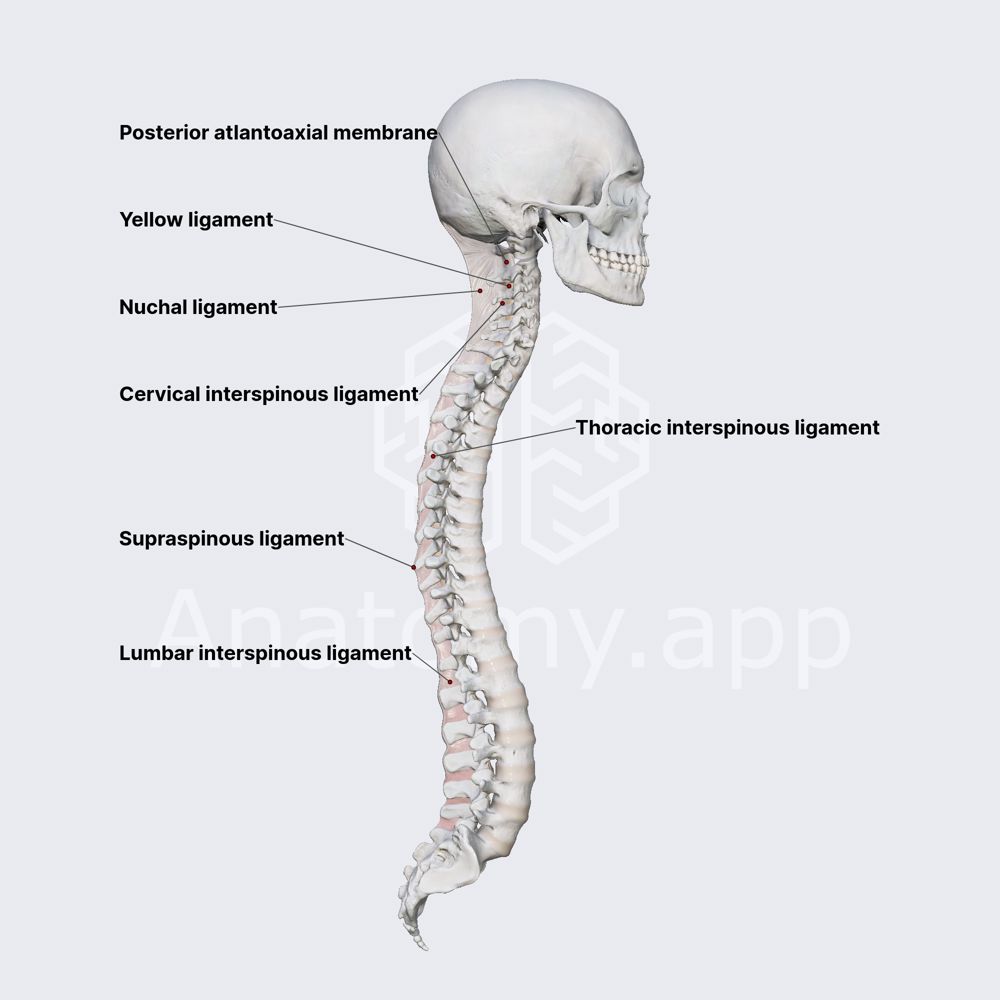

Pure Health - Anatomy 101 - Supraspinous ligament and interspinous ligament 📚 The supraspinous ligament and interspinous ligament work together to limit flexion of the spine by limiting separation of the spinous

DOCS - The interspinous ligament is located between the spinous processes of adjacent vertebrae in the spine. It extends from the base of one spinous process to the apex of the next,